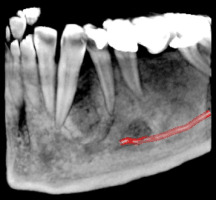

3D скенер на зъби – сектор

Чрез използването на модерната CBCT технология (Cone Beam Computer Tomography) се сканира триизмерен образ на част от челюстта, обхващаща до четири зъба. Този образ може лесно да се обработва. Разглеждането на структурата в 3-те различни равнини помага за прецизната диагностика. Изследването е подходящо за диагностициране на заболявания на зъбите, при ендодонтско лечение, както и за поставяне на единични импланти и др.